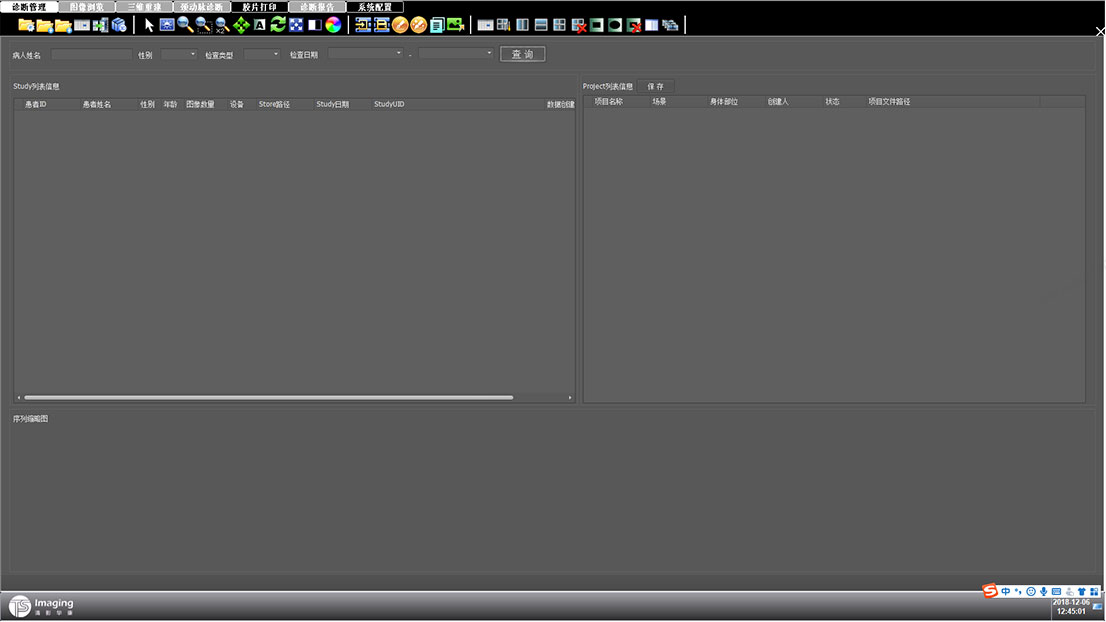

診斷管理原型

三維重建原型

頸動脈診斷原型